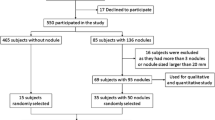

Study participants

233 consecutive participants (mean age 58.5 ± 5.7 years) were recruited for our lung cancer screening program. Inclusion criteria were selected to allow for comparison with other lung cancer screening programs, namely, the US National Lung Screening Trial and the German LUSI-Trial (National Lung Screening Trial Research Team et al. 2011; Becker et al. 2012). General inclusion criteria were age 50–70 years, as well as long-term nicotine abuse (at least 15 cigarettes per day for at least 25 years, or at least 10 cigarettes per day for at least 30 years); participants were active smokers or had quitted smoking for not more than 10 years (Becker et al. 2012). Nine of 233 participants only obtained low-dose CT (LDCT) due to contraindications for magnetic resonance imaging (MRI), eight of them because of claustrophobia, and one because of a cochlear implant. A total of 224 participants underwent LDCT and MRI within the same day or week.

According to magnetic resonance imaging (MRI), 31 of 224 participants had a positive screening result leading to immediate recall or short-term follow-up. Hence, the MRI-based early recall rate was 13.8%. The early recall rate for low-dose CT (LDCT) as reference was slightly lower (29 of 233 participants, 12.5%).

Following Lung-RADS recommendations and based on an interdisciplinary consensus decision, histology (biopsy or surgery) was obtained in eight of 224 cases for MRI (biopsy rate of 3.6%) and in eight of 233 cases for LDCT (biopsy rate of 3.4%). The cases with recommendations for biopsy were identical for MRI and LDCT.

According to LDCT, 110 of 224 participants showed pulmonary nodules. MRI accurately determined that nodules were present in 86 of these 110 cases (78.2%).

The incidence of bronchial carcinoma diagnosed by lung cancer screening in the first year was 3.4% in our study population. The MRI-based early recall rate was 13.8 with 74.2% cases being a false-positive baseline screening result. Both rates are significantly lower compared to reported data from the US National Lung Screening Trial (28 and 96%) (National Lung Screening Trial Research Team et al. 2011), the German LUSI study (22 and 95%) (Becker et al. 2012), and the Dutch/Belgian NELSON study (21 and 95%, applied to the definition of a positive screening results in our study) (van Klaveren et al. 2009). The lower rates are mainly attributable to the fact that the nodule size threshold for early recall was 6 mm in our study, while it was 4 mm in the National Lung Screening Trial and 5 mm in the LUSI study and the NELSON study, respectively (National Lung Screening Trial Research Team et al. 2011; Becker et al. 2012). However, it must be considered that the authors of the NELSON study defined a test positive when non-calcified nodules had a solid component > 500 mm3 (> 9.8 mm in diameter) and when nodules with a solid component of 50–500 mm3 (4.6–9.8 mm in diameter) showed a volume-doubling time of less than 400 days in 3-month follow-up. Hence, according to their definition, 2.6% of the participants had a positive test result with a sensitivity of LDCT-screening for the detection of lung cancer of 94.6% (van Klaveren et al. 2009).